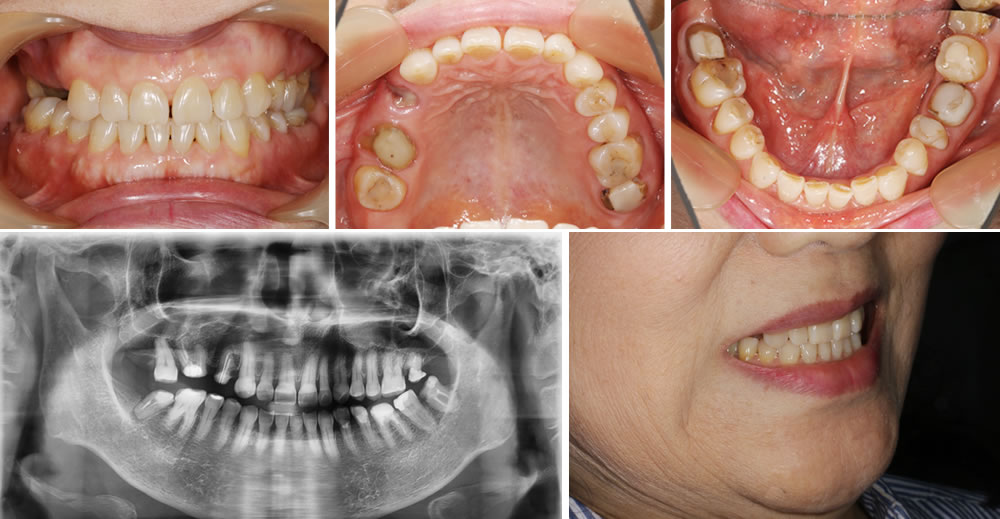

こちらは右上の歯茎が痛いという主訴で来院された患者さまです。

初診時の状態

10年以上前に金属が嫌で右上の金属の被せ物を除去してもらって、そのままになっているとのことでした。しっかり噛めるようにしたいが金属には抵抗があるので金属は入れたくないとの要望がありました。

こちら患者さまは、金属が口腔内に入ったままの状態が嫌で、被せ物を外した状態で放置していた歯が多数あり、奥歯に保存不可能な歯が残っているという状態でした。しっかり噛めるようにしたいという要望があり、インプラント治療を提案しましたが、金属に対して抵抗感が強かったため、インプラント治療は行いたくないとの事でした。